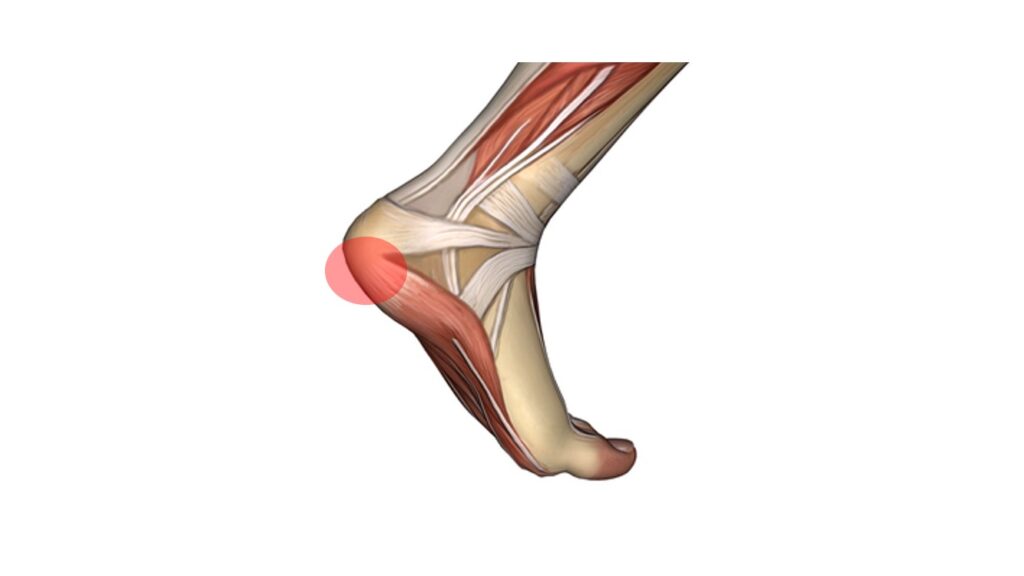

פציעה זו שמערבת את הגיד היא פציעה שכיחה שגורמת לכאב ממוקם על פני הגיד, בחלק האחורי של הקרסול או מעליו, כתלות באזור המעורב של הגיד. הכאב יתחיל ככאב תלוי פעילות, אך לאחר מכן יכול להיות גם כאב לאחר פעילות ואף כאב במנוחה/הליכה רגילה. לעיתים תופיע נפיחות מקומית.

פציעה זו נובעת מכשל בתהליכי הריפוי המקומיים בתגובה לעומסים החוזרים על הגיד וסביבתו. מדובר בעיקר על תהליך שחיקתי (ניווני) בגיד שלעיתים מלווה גם בתהליכים דלקתיים. גורמים שהוזכרו בהקשר לפציעה זו כוללים: אספקת דם פחותה לאזור, חולשה שרירית, מבנה כף רגל עם קשה גבוהה, אי יציבות של הקרסול, שימוש בתרופות כדוגמת אנטיביוטיקה ממשפחת הפלורוקינולונים ועוד.

במסגרת תהליך האבחון יש לשלול סיבות אחרות לכאבים דומים כגון: תגובת מאמץ של העצם, תסמונת צביטה אחורית בקרסול, אי יציבות קרסול ועוד. על כן, חשוב לעבור הערכה רפואית מקצועית של מומחה בתחום.

הטיפול מבוסס על הימנעות ממאמצים המחמירים את הכאב ופיזיותרפיה שתתמקד בעבודה על גמישות (מתיחות) וחיזוק (אקסצנטרי) של שרירי השוק וכף הרגל בדגש על שרירי התאומים והסוליה. טיפול נוגד דלקת יכול לסייע במצבים החריפים. בהעדר מידע מוכח ניתן לשקול גם טיפולים בגלי הלם, מדרסים או כרית הגבהה לעקב, טיפול מקומי מסוגים שונים ועוד. חשוב מאוד להיות סבלניים ולנהל עומסים בצורה נכונה עד חזרה לפעילות מלאה ולעיתים ידרשו שבועות ארוכים עד חודשים של שיקום.

במקרים עקשניים ניתן לשקול טיפול בהזרקות. הזרקה של חומרים סטרואידים לא מומלצת לגיד זה בשל הסכנה לפגיעה בגיד לאחר ההזרקה, עד כדי קרע שלו. הזרקה של חומרים ביולוגים כדוגמת פלסמה עשירת טסיות (PRP) היא בטוחה יותר ונחשבת טיפול אפשרי בשילוב עם פיזיותרפיה ותרגילים, אם כי לא קיימות הוכחות מובהקות על עליונות טיפול זה על טיפולים אחרים.

במקרים בהם הטיפולים הלא-ניתוחיים כשלו, ישקל טיפול ניתוחי המותאם לאזור הפגוע בגיד.